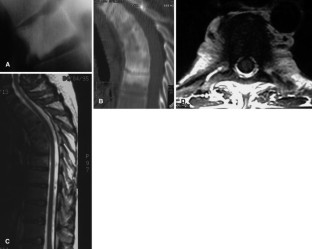

SAPHO: syndrome or concept? Imaging findings

The SAPHO syndrome was a term coined to include a variety of musculoskeletal disorders associated with skin conditions, mainly palmoplantar pustulosis and acne conglobata. It is more correctly a spectrum which includes the following: skin lesions, osteoarticular manifestations of synovitis hyperostosis and osteitis affecting particular target sites, and·a clinical course marked by relapses and remissions. The major sites of involvement are the anterior chest wall, the spine, long bones, flat bones, and large and small joints. The distribution and severity of involvement varies from the adult to the pediatric form of chronic recurrent multifocal osteomyelitis (CRMO). The diagnosis of SAPHO syndrome is not difficult when the typical osteoarticular lesions are located in characteristic target sites. The diagnosis is more difficult if atypical sites are involved and there is no skin disease.